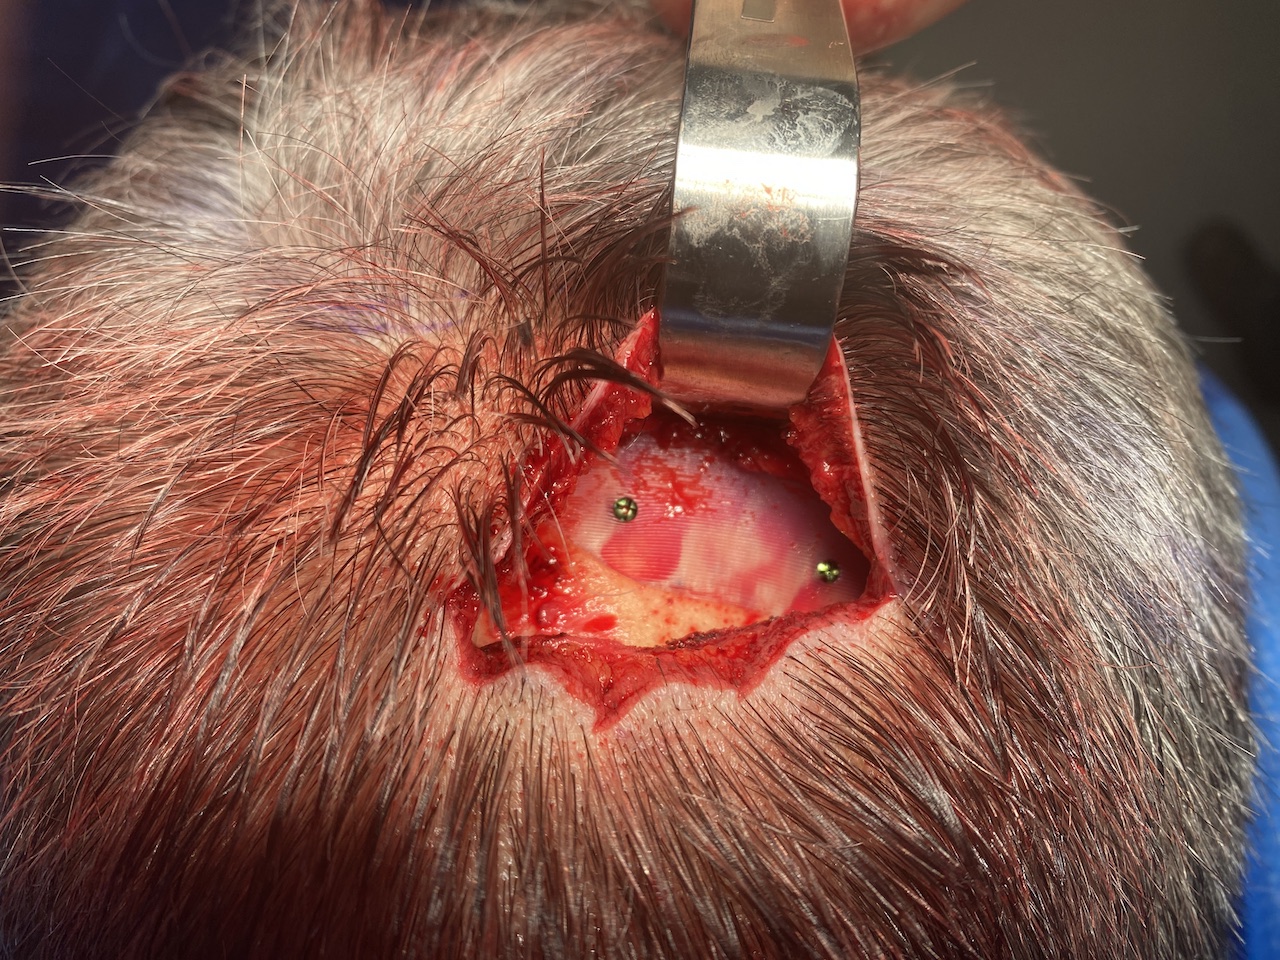

Desire for reduction of prominent occipital knob deformity.

Intraoperative result from occipital knob skull reduction through a direct small scalp incision.

Desire for reduction of prominent occipital knob deformity.

Intraoperative result from occipital knob skull reduction through a direct small scalp incision.